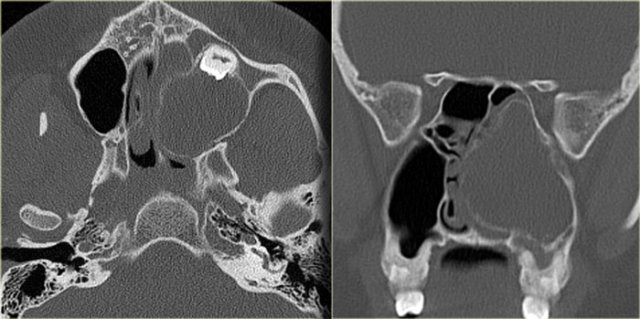

On the left an axial MR-image showing a mass in the ethmoids.

The MRI shows no intracranial extension.

What is the next step?

Sinonasal carcinoma Sinonasal carcinoma

A CT is necessary to determine the integrity of the adjacent bone.

Notice the bony destruction of the fovea ethmoidalis and planum sphenoidale.

This indicates that this is a malignant lesion and biopsy demonstrated an adenocarcinoma.

If the patient is a surgical candidate, frontal endoscopic sino-nasal surgery won't be enough and a cranio-facial take-down will also be required.